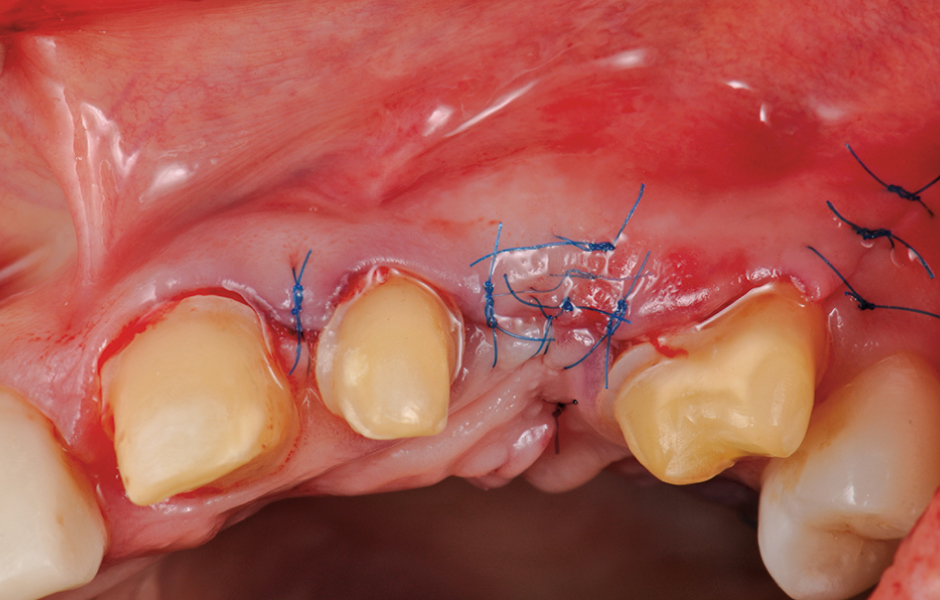

Kromě toho měla být před zahájením protetického ošetření provedena korekce emergence profilu gingivy. V důsledku zánětu dásní a chybějícího zubu 23 došlo v této oblasti k výrazné recesi dásně. Tento stav byl chirurgicky napraven, aby bylo později možno dosáhnout přirozeně působící náhrady ve frontálním úseku chrupu (obr. 3, 4).